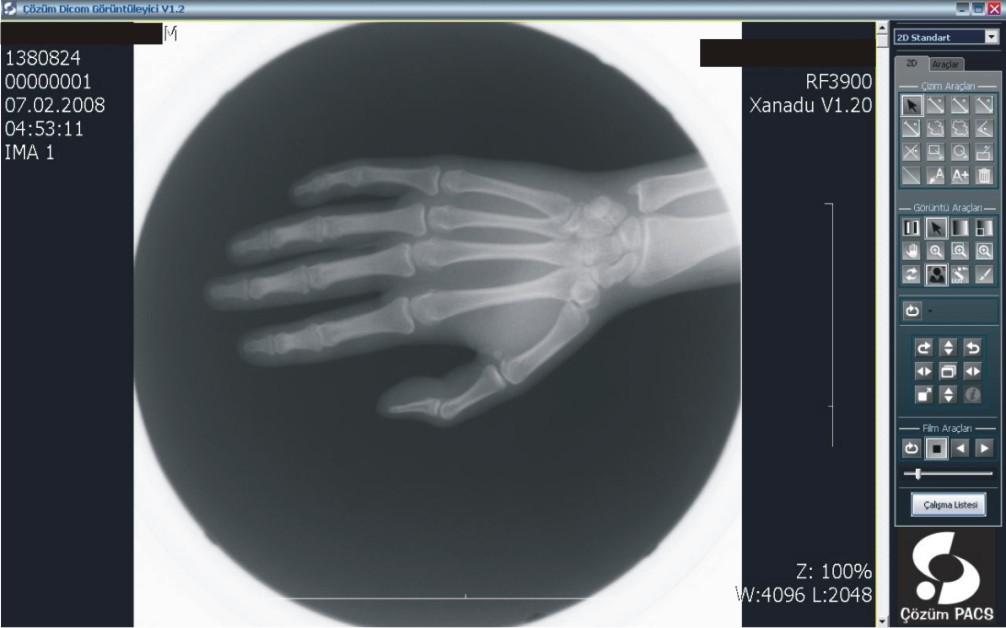

Hastanemizde bilgi yönetim sistemi olarak Çözüm HBYS'yi (Hastane Bilgi Yönetim Sistemi) kullanıyoruz. Güçlü bir entegrasyon sağlamak adına uluslararası standartlara haiz, tamamı Türk mühendislerine ait tek PACS olma özelliğindeki Çözüm PACS'ı tercih ettik.

PACS ile, dijital olarak elde edilen panoramik ve lokal radyolojik görüntüler (ultrasonografi, doppler, magnetik rezonans, tomografi v.b. cihazlardan elde edilen veriler) çevrimiçi ortamlarda dijital arşivleme yöntemleriyle saklanıyor. Kayıpsız bir şekilde, hızlı ve güven içinde saklanan bu görüntüler, gerektiğinde istemcide yeniden görüntülenerek kullanılabiliyor.

Merkezi veri tabanında bilgilerin depolanması ile oluşan dijital arşiv (görüntüler üzerinde işlem yapmaya izin verecek şekilde yüksek çözünürlükte saklandığı için ölçüm ve tanıya ilişkin işlemler kolaylıkla yapılabiliyor), bilgilerin yeniden kullanılmasını arşivlenen bilgilerin modern tanı yöntemleri ile incelenmesini sağlıyor. Dijital görüntüler üzerinde işlem ve ölçüm yapılabiliyor. Görüntüler ve raporların her an, her yerde (tüm iş istasyonları üzerinden sorgulama yapılarak) ulaşılabilir olmasına ve görüntü işleme ve ölçüm (mesafe, açı, uzunluk, yoğunluk) yapılabilmesine imkan sağlıyor.

PACS, tanı ve teşhislerde daha doğru sonuçlar elde edilmesini sağlayarak  sonuçları  yorumlama ve raporlama süresini hızlandırıyor. Görüntülerin karşılaştırılması ve radyolojik bulguların geriye dönük değerlendirilmesi, karşılaştırmalı raporların incelenmesi, hekimin hastalığın gelişim sürecini daha iyi kavramasını ve doğru teşhisi daha hızlı bir şekilde koyabilmesini sağlıyor. Yedeklenen PACS görüntüleri istenildiğinde hastalara CD-DVD halinde veriliyor.